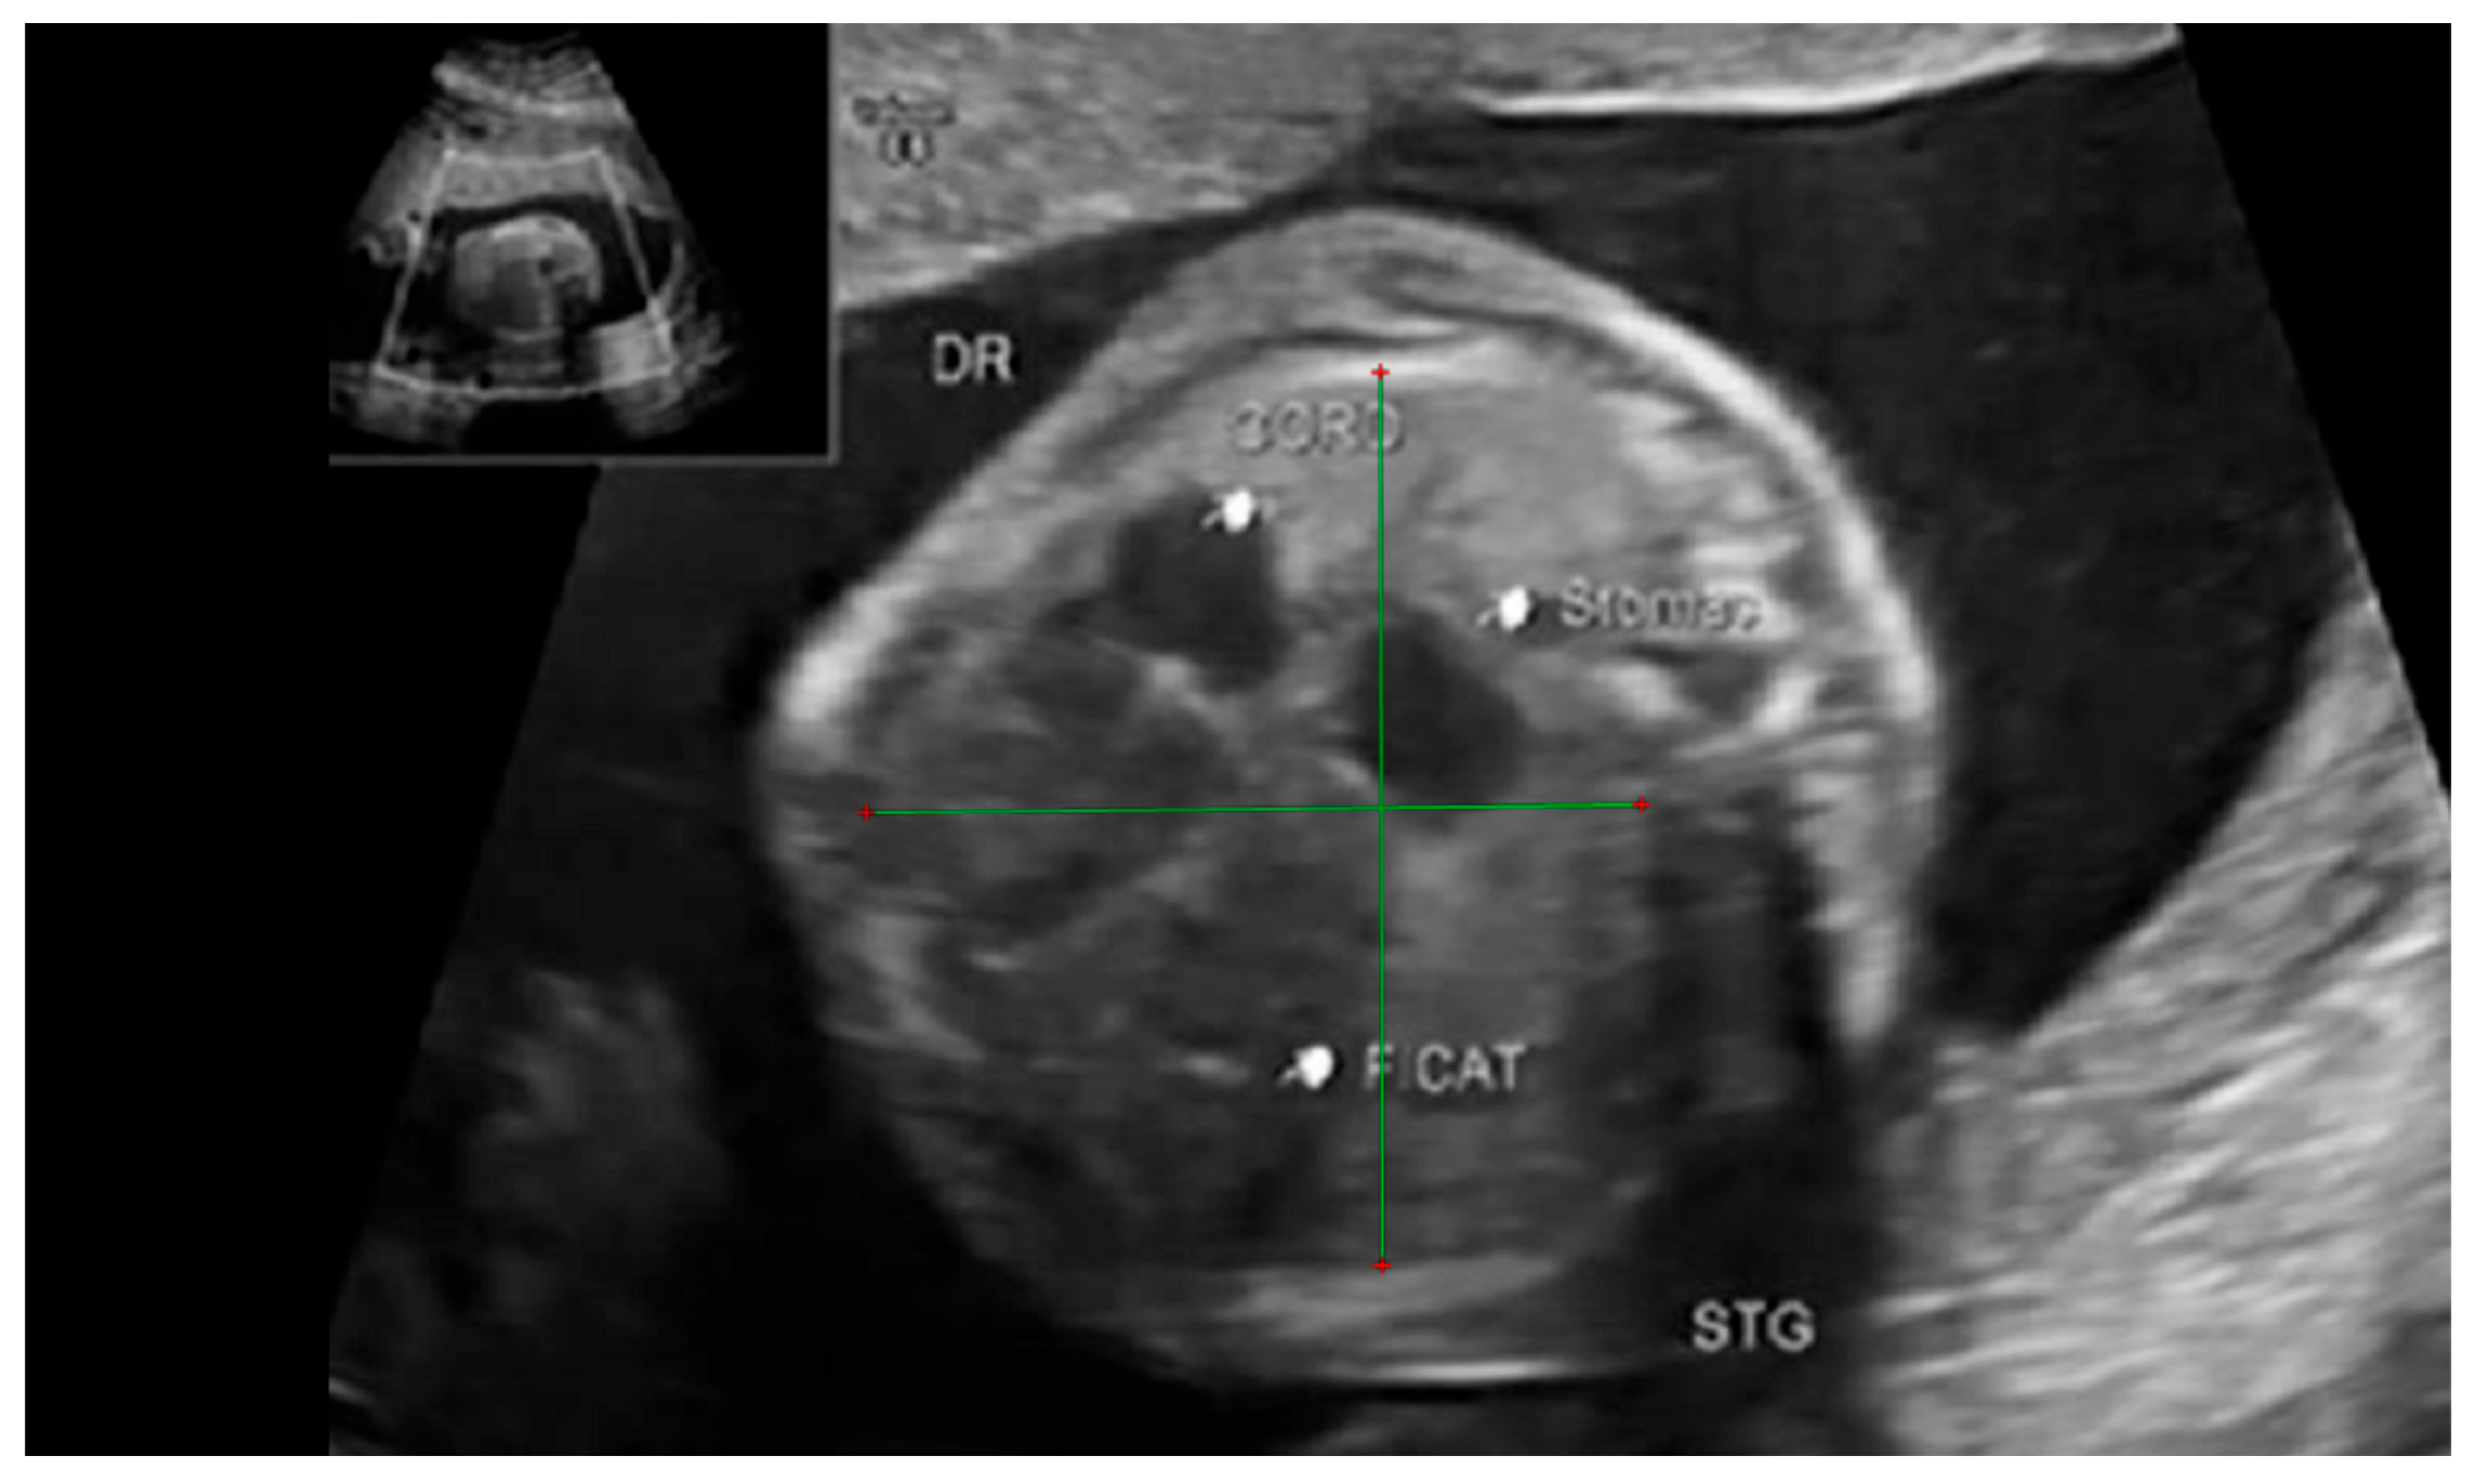

Figure 2. Ultrasound axial four-chamber image of the fetus showing the tracing method for calculating the LHR, using the RadiAnt DICOM Viewer program, version number 2022.1.1. The green line represents the lug area on the nonherniated side.

Fetal lung volume was calculated by using a new method to reduce the overestimation of the lung volume. The first step was tracing the lung area of both lungs on each slice. We then obtained the mean between every 2 consecutive slices and multiplied the value by the distance between them. Finally, we calculated the sum of all these values and obtained the TLV for each lung. For easier viewing of this parameter, we calculated the total lung volume ratio (TLVR) by calculating the ratio between our observed value and the expected lung volume values obtained from reference articles that measured standard values for lung volumetry using MRI. To be more precise, we looked at the studies of Meyers et al., Rypens et al., Osada et al., and Sefidbakht et al. [16,17,18,19] and calculated a mean from them that was used as our reference. Figure 1 and Figure 2.

We also compared our findings with the expected values obtained by using ultrasound volumetry as per the work of Lian et al. [20].